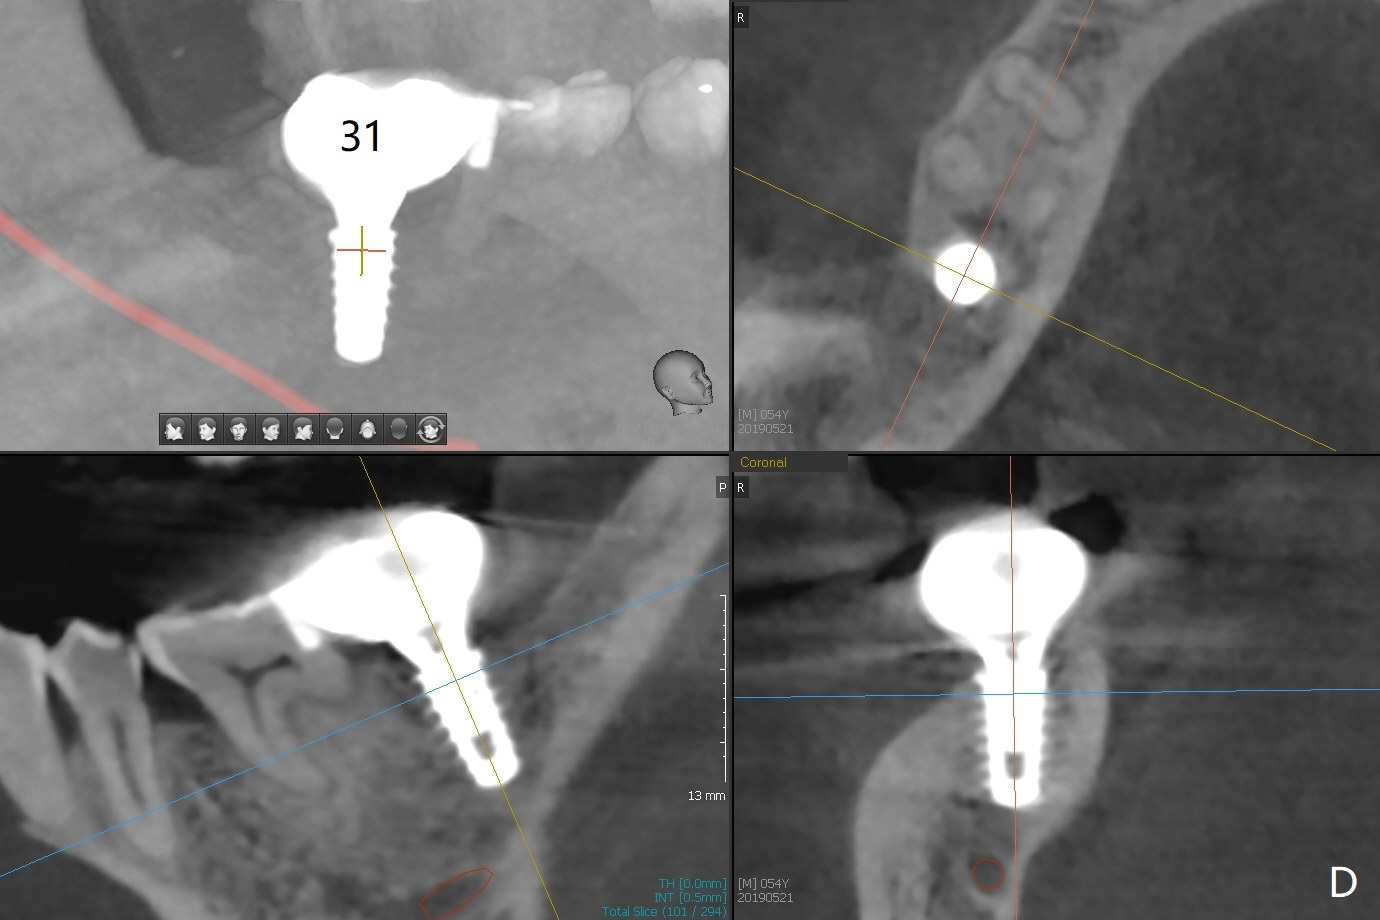

A 54-year-old man remains difficult in mastication in spite of implant placement at #14 and 31 (Fig. A, B, E, including screw loosening (poor trajectory at #14)). In addition to 2 more implants at #15 and 18 with guide, malocclusion seems to be necessary to be addressed (Fig.1-5). It appears that UR, LL4 should be extracted for orthodontic treatment (Fig.6-10). To reduce screw loosening, IS guide will be used to place IBS (5x9mm) and tissue-level (5x11mm) implants at #15 (PRF)and 18, respectively. If the one at #14 or 15 keeps loosening, splint #14 and 15 crowns. In fact the patient agrees with limited ortho (UR7 cross bite).